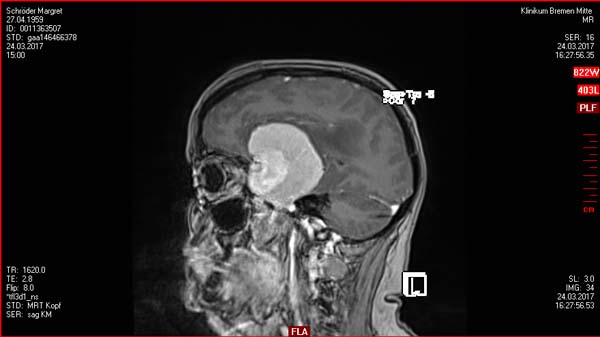

30.03.2017: OP

• Komplette Resektion des ausgedehnten links temporalen Meningeoms (Neurochirurgie Bremen).

initiale Histologie: Meningeoms WHO-Grad II.

Schön zu sehen war, dass der bestrahlte Tumor kein Wachstum hatte - siehe Bilder vor dem Text.